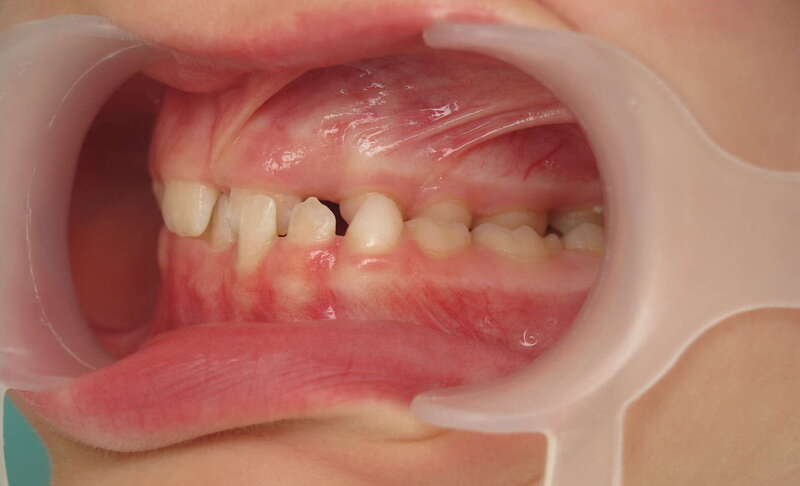

Cas n°3 traité par aligneurs (interception) - enfant

Intervenir dès 8 ans avec cette approche offre des bénéfices structurels :

• Symétrie Faciale : En éliminant le glissement de la mâchoire, on assure que le visage se développe de manière droite et harmonieuse.

• Confort Articulaire : Le recentrage prévient les tensions et les pathologies futures des articulations de la mâchoire (douleurs, craquements).

• Expérience Positive : L'absence de douleur et la simplicité des aligneurs favorisent une excellente acceptation du traitement par l'enfant.

• Simplification du futur : "Remettre la croissance sur les rails" permet souvent d'éviter des traitements beaucoup plus complexes (voire chirurgicaux) à l'adolescence.